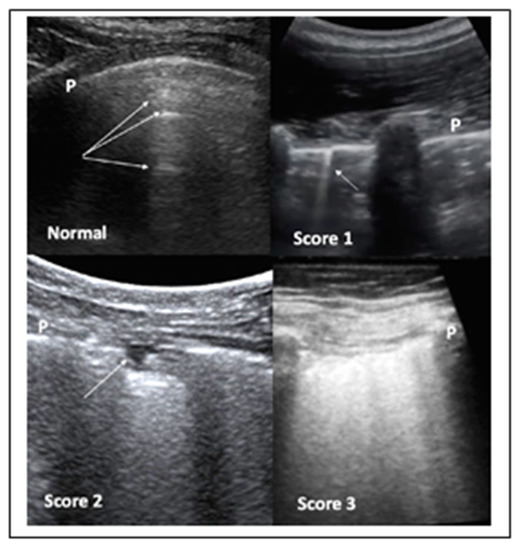

It has been also suggested that LUS should involve two operators in the acquisition protocol in order to reduce their exposure time to COVID-19 patients, with the first scanning and the second one storing the images. Both convex and linear probes can be used. Moreover, the standard LUS investigation is composed by 14 intercostal windows, seven for each side: three posteriorly along the paravertebral line; two laterally along the mid-axillary line; two anteriorly along the mid-clavicular line, these latter ones below and above the inter-nipple line, respectively. The LUS in patients not able to maintain a sitting position can be performed in lateral decubitus. COVID-19 pneumonia can be also scored for severity by LUS (Figure 3).

Figure 3.

LUS aspects of COVID-19 pneumonia. Top left panel—LUS in normal cases. The pleura line (P) is sliding, mobile at breathing, and hyperechoic. The arrows indicate the A lines, which are horizontal, not mobile lines below the pleura line. Top right panel—LUS in COVID-19 patient: the presence of irregularities of the pleura line (P) coupled with vertical, comet-like, mobile B lines (arrow) become apparent. These findings are frequently bilateral and alternate with areas of normality, as shown in this panel. Bottom left panel—LUS in COVID-19 patient: the pleura line P is broken. Subpleural triangular dark area (arrow) with a hyperechoic floor is defined a subpleural consolidation area. Bottom right panel—LUS in COVID-19 patient: the so-called “white lung”.

The introduction of the severity score leads us to prefer LUS to both swab-PCR and CT scan for the following clinical needs:

- When following-up the evolution of COVID-19 pneumonia, in situations where the use of a CT scan would expose the patient to an excess of radiation.

- When monitoring longitudinally health care professionals. Since it is expected that the pandemic will continue for some time, it will also be necessary to monitor medical staff. For this purpose, LUS would be ideal. Based on the incubation time, it would seem reasonable to repeat the survey every two weeks.